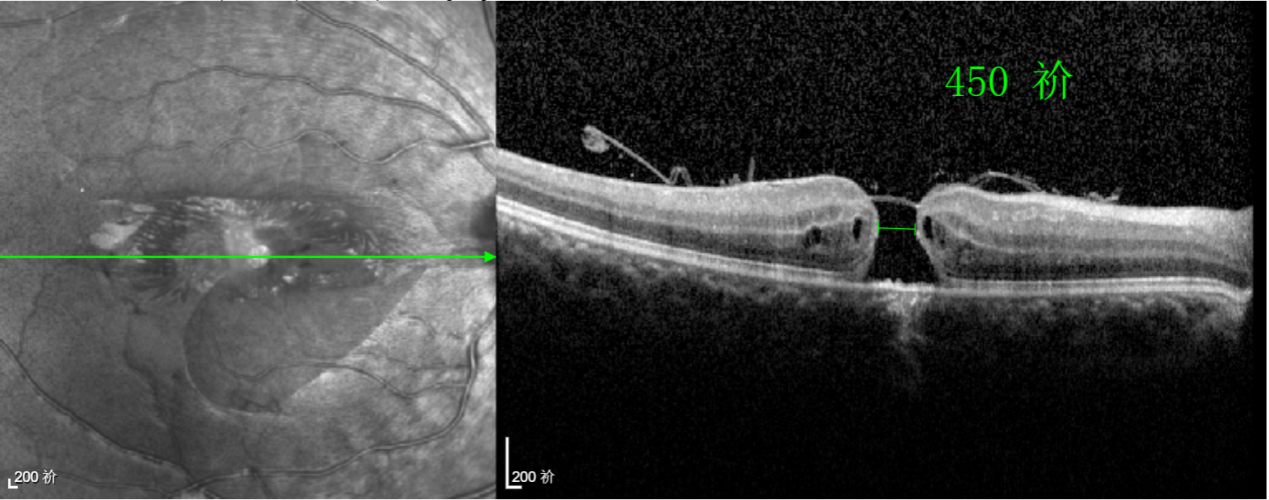

經(jīng)過(guò)詳細(xì)的檢查和評(píng)估,王曉波主任決定采用“內(nèi)界膜翻轉(zhuǎn)覆蓋聯(lián)合粘彈劑固定術(shù)”為誠(chéng)誠(chéng)進(jìn)行治療。

術(shù)中,醫(yī)生精細(xì)剝離黃斑區(qū)的內(nèi)界膜后,并非直接丟棄,而是巧妙地給它翻個(gè)面,讓它變成一塊天然“創(chuàng)可貼”,嚴(yán)密覆蓋在黃斑裂孔的表面。覆蓋的內(nèi)界膜像微型支架一樣撐住裂孔邊緣,防止它擴(kuò)大;同時(shí),這層膜本身含有能促進(jìn)生長(zhǎng)的“養(yǎng)分”,能顯著刺激裂孔周?chē)囊暰W(wǎng)膜組織像爬山虎一樣快速生長(zhǎng)、蔓延過(guò)來(lái),最終把裂孔“補(bǔ)”好。

除此之外,利用自體組織覆蓋為黃斑裂孔提供了理想的愈合環(huán)境,裂孔閉合速度顯著快于傳統(tǒng)方法。誠(chéng)誠(chéng)接受手術(shù)24小時(shí)后,檢查可見(jiàn)內(nèi)界膜瓣位置良好;術(shù)后1個(gè)月,黃斑裂孔已經(jīng)閉合,視力恢復(fù)到0.5;術(shù)后兩個(gè)月,視力進(jìn)一步提升到0.7。